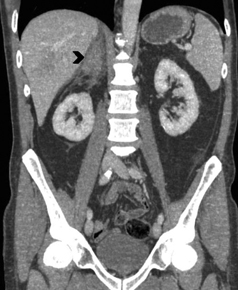

En la TC no contrastada las glándulas suprarrenales normales son homogéneas y simétricas, con una densidad muy similar a la del parénquima renal adyacente (Figura 1 a). Con un medio de contraste ev la glándula suprarrenal se opacifica en forma homogénea, similar al hígado o al bazo (Figura 1 b). Si la cantidad de tejido adiposo retroperitoneal es abundante las glándulas suprarrenales pueden aparecer enteramente rodeadas por grasa y su delimitación es más fácil (Figura 2 a); lo inverso ocurre en pacientes muy delgados con escasa grasa retroperitoneal (Figura 2 b). En RM, en secuencias ponderadas en T1 y T2 convencionales tienen una intensidad de señal homogénea, hipointensa respecto de la grasa adyacente e iso o hipointensa con respecto del parénquima hepático (Figura 3 a y b). En los cortes coronales se aprecia mejor la forma y la posición de las glándulas suprarrenales (Figura 3 c).

Figura 3. Glándula suprarrenal normal en resonancia magnética. (a) Cortes axial ponderado en T1 la señal de la glándula normal (flecha negra) es hipointensa respecto a la grasa retroperitoneal e isointensa respecto al parénquima hepático. (b) Cortes axial ponderado en T2 en que se muestra la glándula suprarrenal derecha (flecha blanca) y (c) corte coronal ponderado en T2 en que se muestra la glándula suprarrenal derecha (flecha blanca) y la glándula suprarrenal izquierda (flecha negra) con similares características de intendidad de señal. 3. Causas y prevalencia de las lesiones suprarrenales